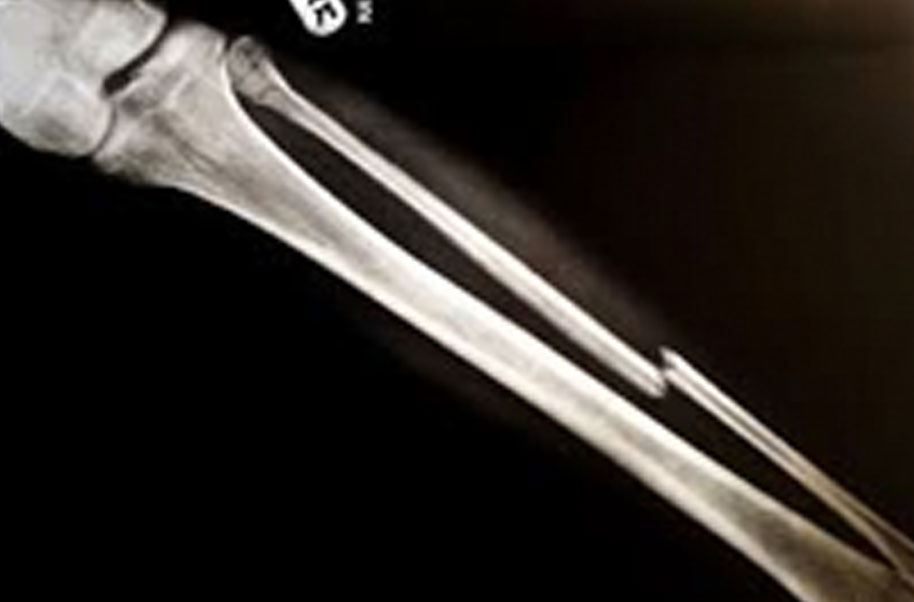

Os Sphenoidale (Broken Bone)

A complete or partial break in a bone.

- Treatment often involves resetting the bone in place and immobilising it in a cast or splint to give it time to heal. Sometimes, surgery with rods, plates and screws may be required.

Causes of bone fractures include trauma, overuse and diseases that weaken bones.